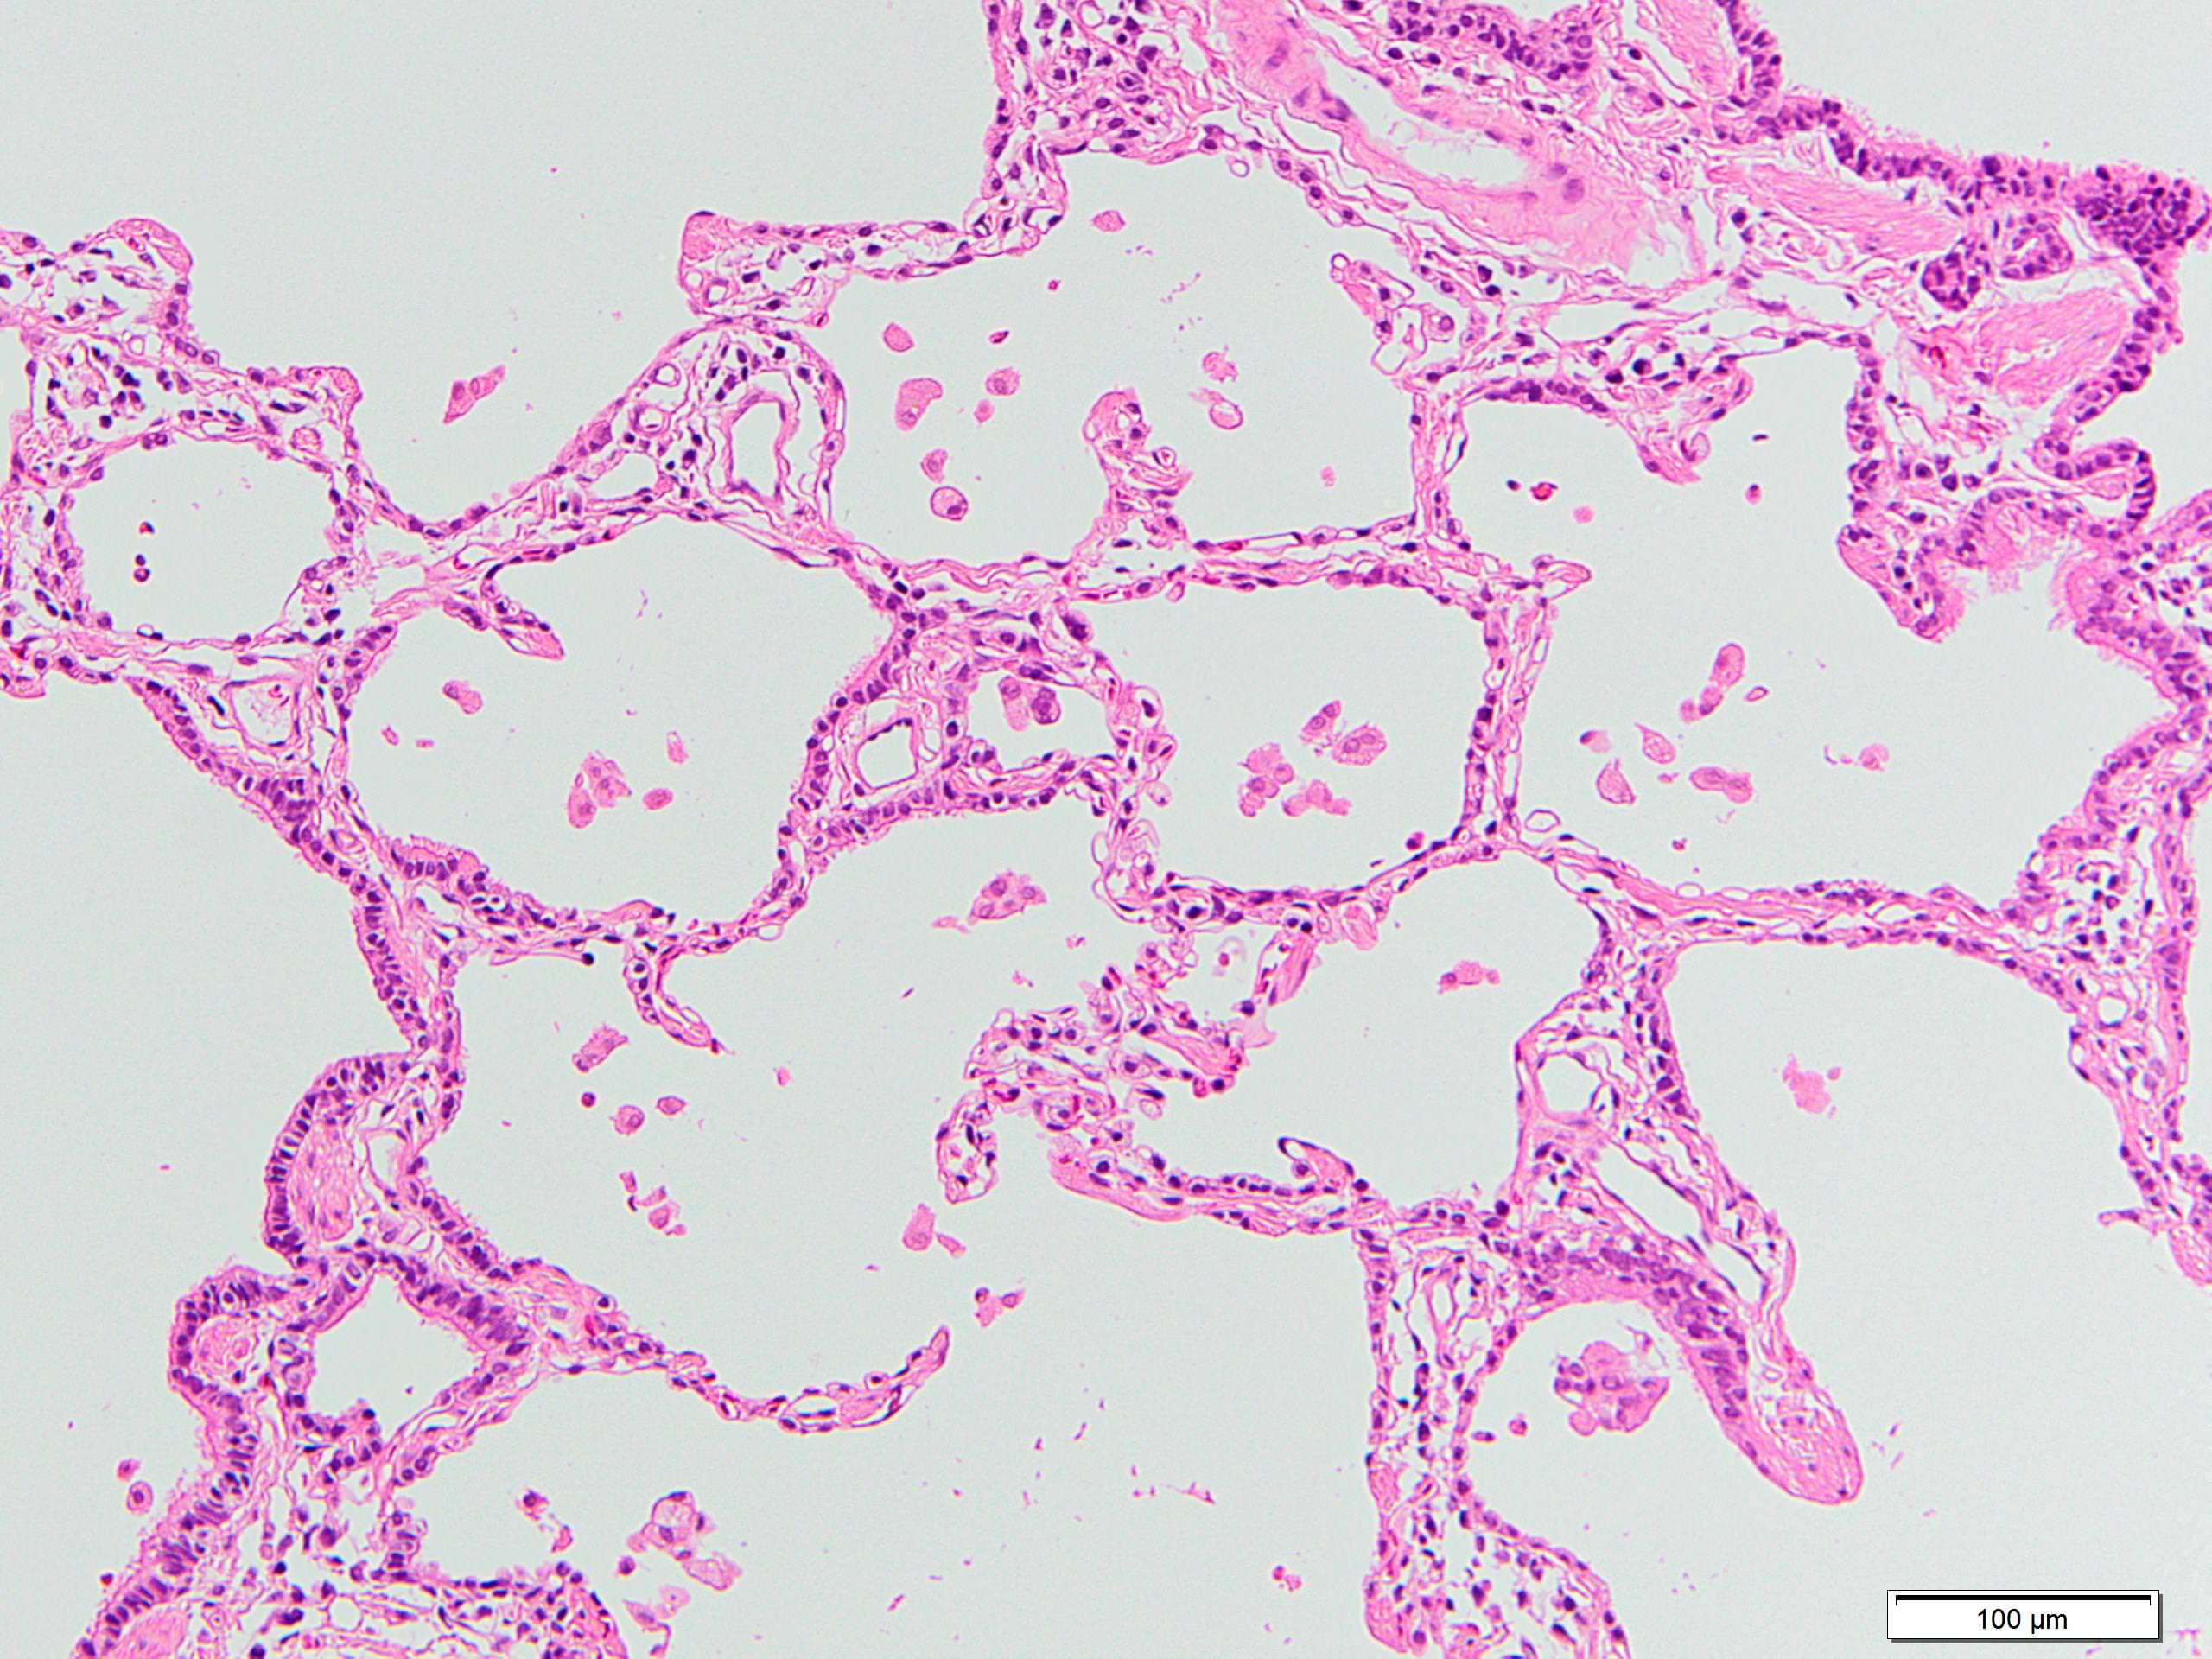

Microscopic (histologic) description

- Since there are few specific findings for NSIP pattern, it is essential to exclude other lung diseases on histology (Am J Respir Crit Care Med 2008;177:1338)

- Characteristic findings of NSIP pattern

- Diffuse and uniform inflammation ("temporal homogeneity") on low power of alveolar wall, bronchovascular bundles and pleura

- There are usually no normal alveolar walls in the affected lobules

- Cellular or fibrotic change

- Lymphocytic or plasmacytic infiltration

- Loose fibrosis

- Lung architecture is frequently preserved

- "Cellular NSIP" or "fibrotic NSIP" can be stated specifically in pathologist report

- Diffuse and uniform inflammation ("temporal homogeneity") on low power of alveolar wall, bronchovascular bundles and pleura

Microscopic (histologic) images

Contributed by Akira Yoshikawa, M.D.

Positive stains

- Elastica van Gieson staining highlights the relative preservation of lung architecture